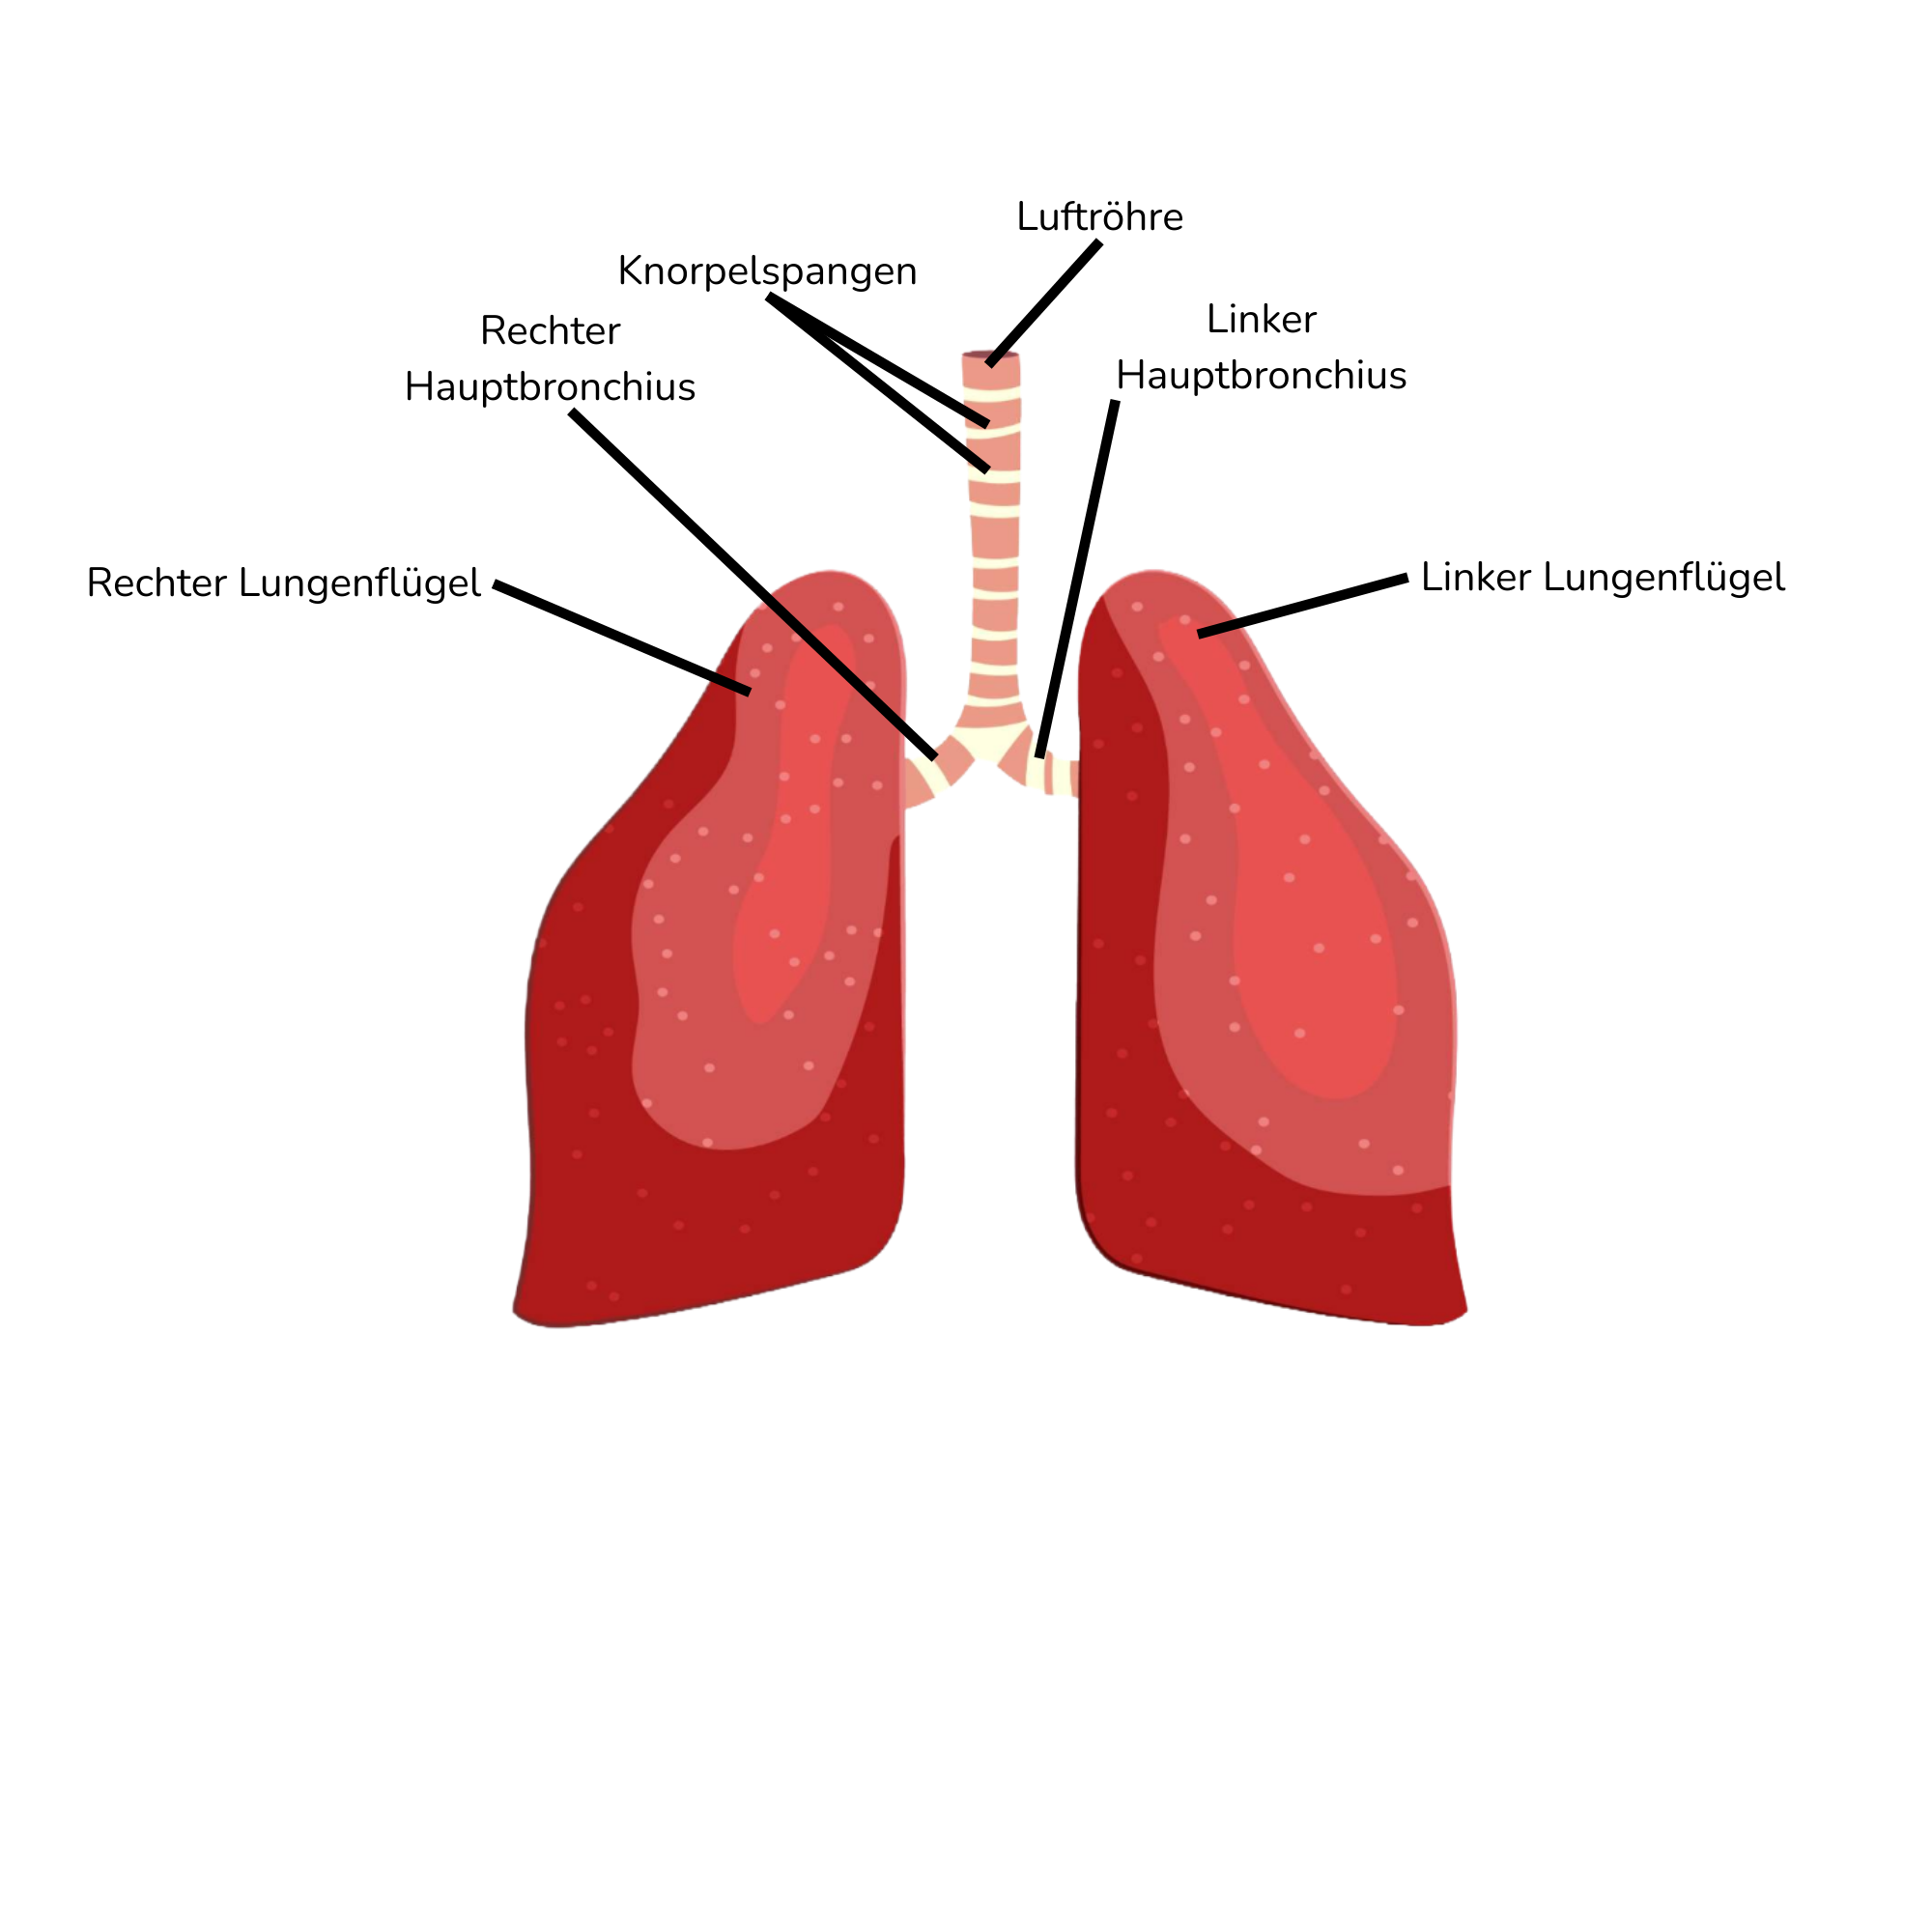

- Lungenflügel: Die Lunge besteht aus zwei Lungenflügeln, die gut geschützt im Brustkorb liegen.

- Luftröhre: Die Luft gelangt über die Nase oder den Mund in die Luftröhre. Sie teilt sich am Ende in die beiden Bronchien, die zu den Lungenflügeln führen.